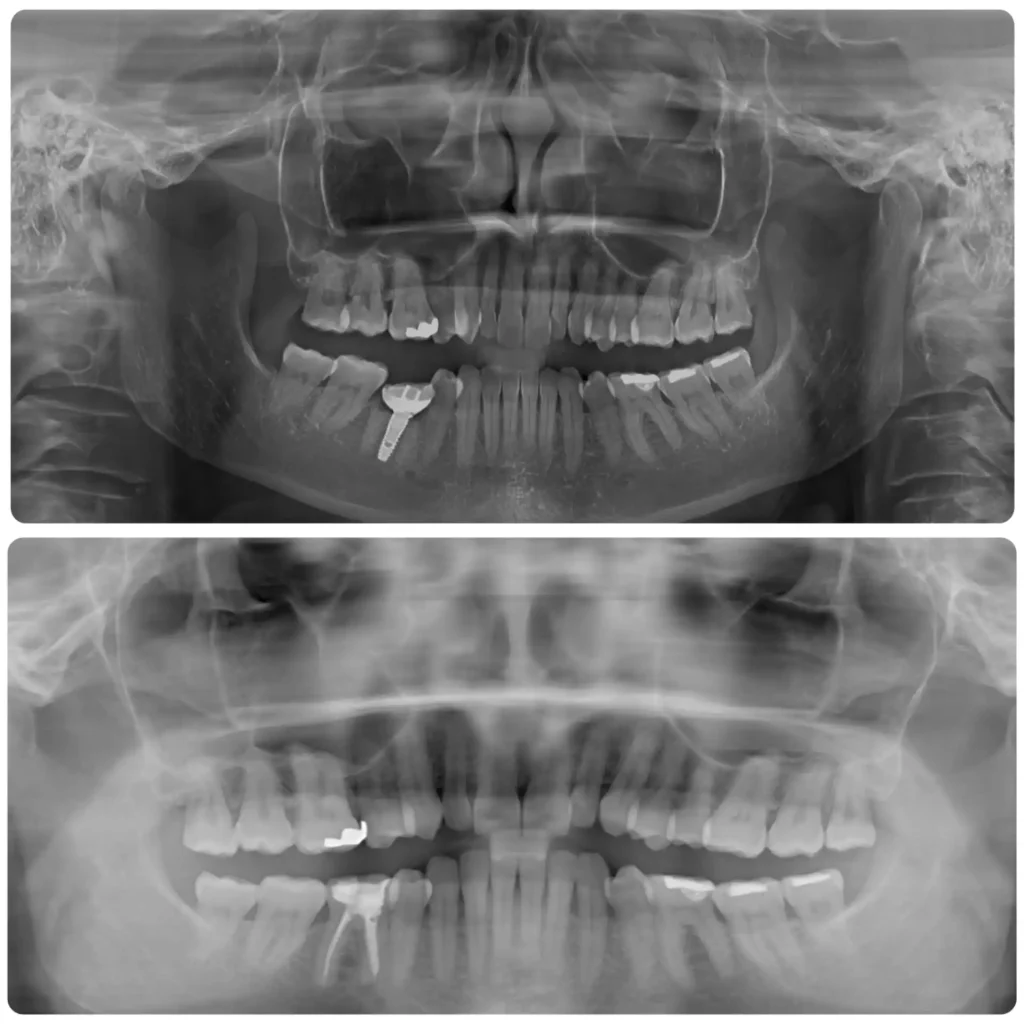

Case studies